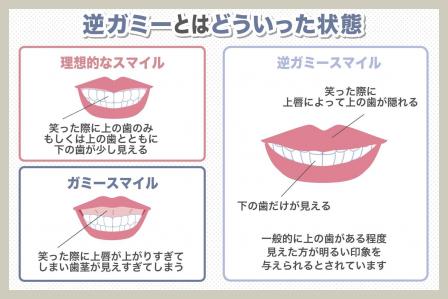

出っ歯とは?上顎前突の特徴と口ゴボ(上下顎前突)との違い

出っ歯は、主に上の前歯(中切歯)が前方に傾いている状態を指します。医学的には「上顎前突(じょうがくぜんとつ)」と呼ばれ、歯の生え方や顎の骨の大きさのバランスによって引き起こされることが多いです。

出っ歯の特徴

- 上の前歯が大きく前方へ傾いている

- 唇を閉じると上唇だけが盛り上がって見える

- 笑ったときに前歯が目立ちやすい

- 前歯が前に出ていることで発音がしづらいことがある(特にサ行)